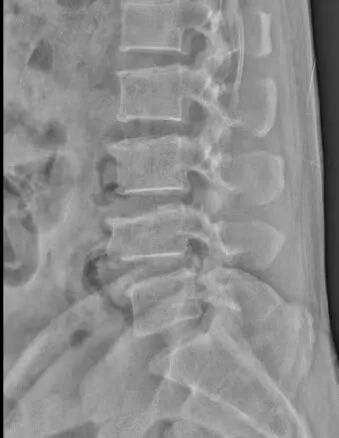

患者江先生,56岁,因外伤4椎体压缩性骨折。为了最大限度减少对患者的创伤,加快其康复,术前科室进行认真讨论,查阅资料,观看手术视频,制订详细的手术计划,于929日在全麻下行微创小切口脊柱后路钉棒系统内固定术治疗腰4椎体压缩性骨折,术后复查X线提示腰椎高度恢复,内固定位置正常。

姚主任介绍道,传统椎弓根内固定植骨融合术采用切开皮肤,剥离肌肉,显露椎体结构后,植入椎弓根螺钉固定,存在创伤大(约10厘米)、椎旁肌肉剥离广泛、术中出血多(一般出血约300毫升)、术后切口引流量大(一般约200毫升)、术后切口疼痛、恢复期长等。而微创经皮椎弓根钉棒内固定植骨融合术因其手术创伤小(约2厘米),术中出血少(约20毫升),不剥离椎旁肌肉,术后切口无需引流,无术后切口疼痛,可早期下地进行功能恢复,是近年来发展起来的新技术,也是目前微创治疗腰椎滑脱、胸腰椎骨折、椎管狭窄、肿瘤等脊柱疾病的一种先进手术方式。经皮椎弓根钉棒系统内固定术微创技术,对手术技术要求比传统手术方式更高,术前需要非常周密的计划,根据患者的影像资料做非常精确地测量和定位,更需要手术医生具有非常娴熟的开放椎弓根钉棒系统内固定技术及经皮椎弓根穿刺技术。